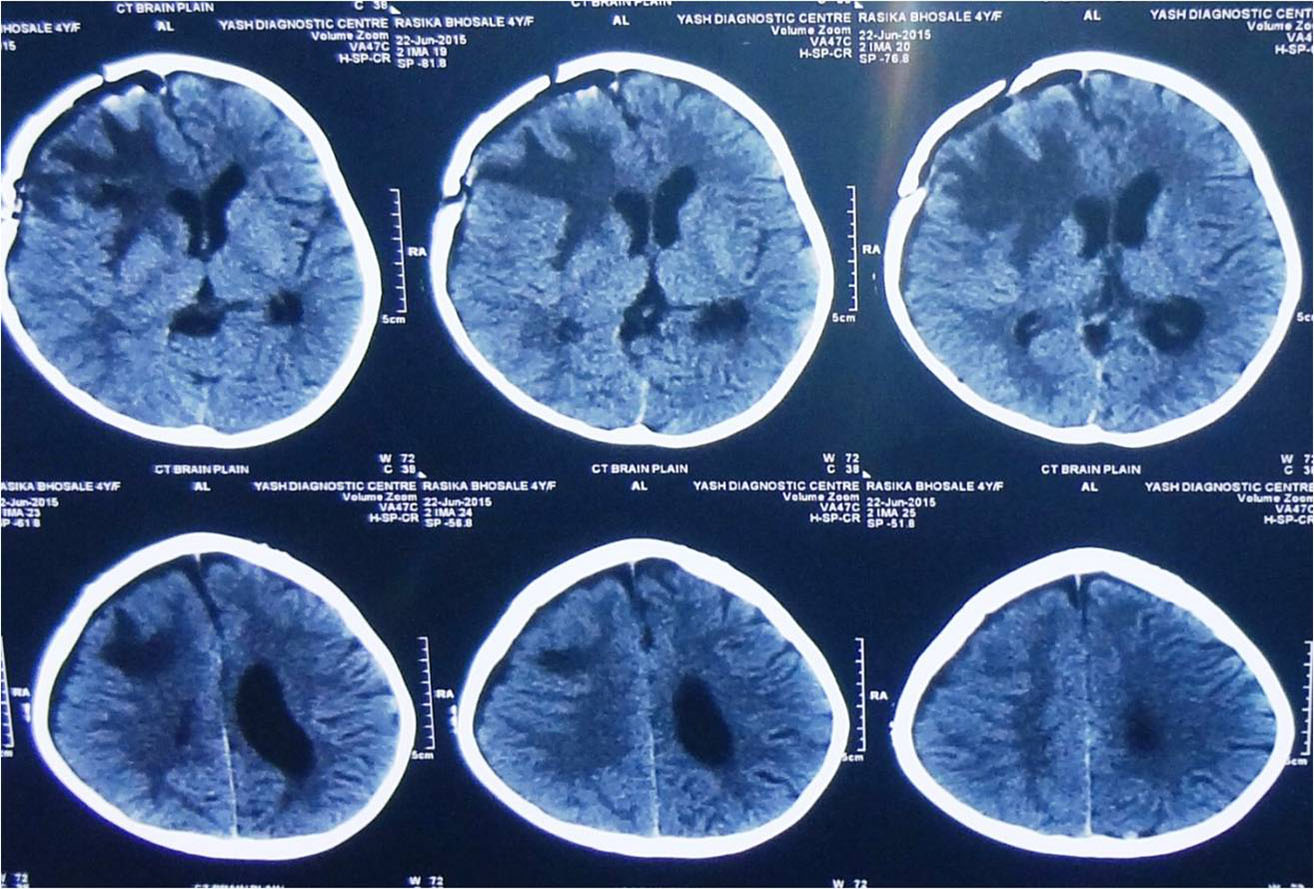

Traumatic Brain injury is defined as damage to the brain resulting from external mechanical force,

commonest causes of brain injury are vehicular accidents, assaults, and accidental falls etc.

Brain injuries can be minor or major life threatening. The signs and symptoms depend on the severity of injury.

It is important to begin emergency treatment within the so-called "Golden Hour" following the injury.

Minor injuries are usually treated with medications and constant monitoring. Moderate to severe injuries require treatment in neurosurgical ICU and may require emergency surgery.